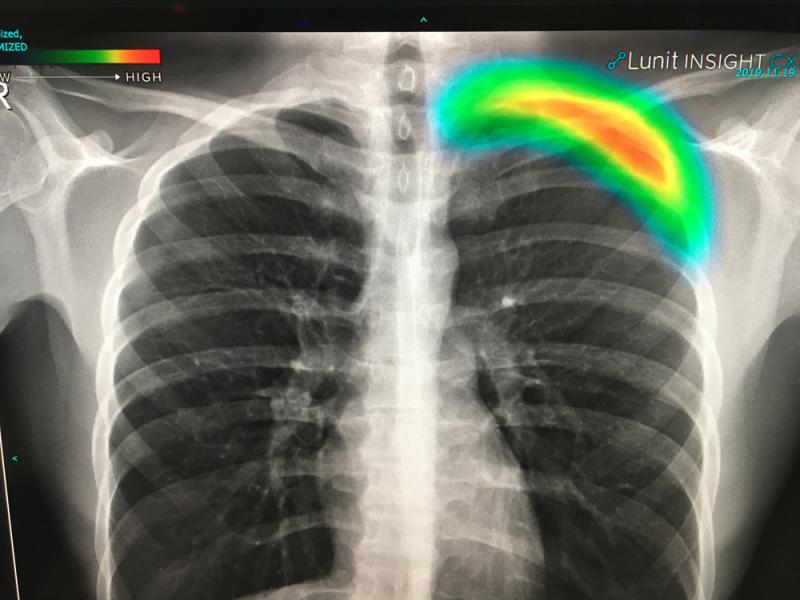

Interventional radiology uses tools like angiography X-ray systems to provide minimally invasive medical diagnosis and treatment using images.